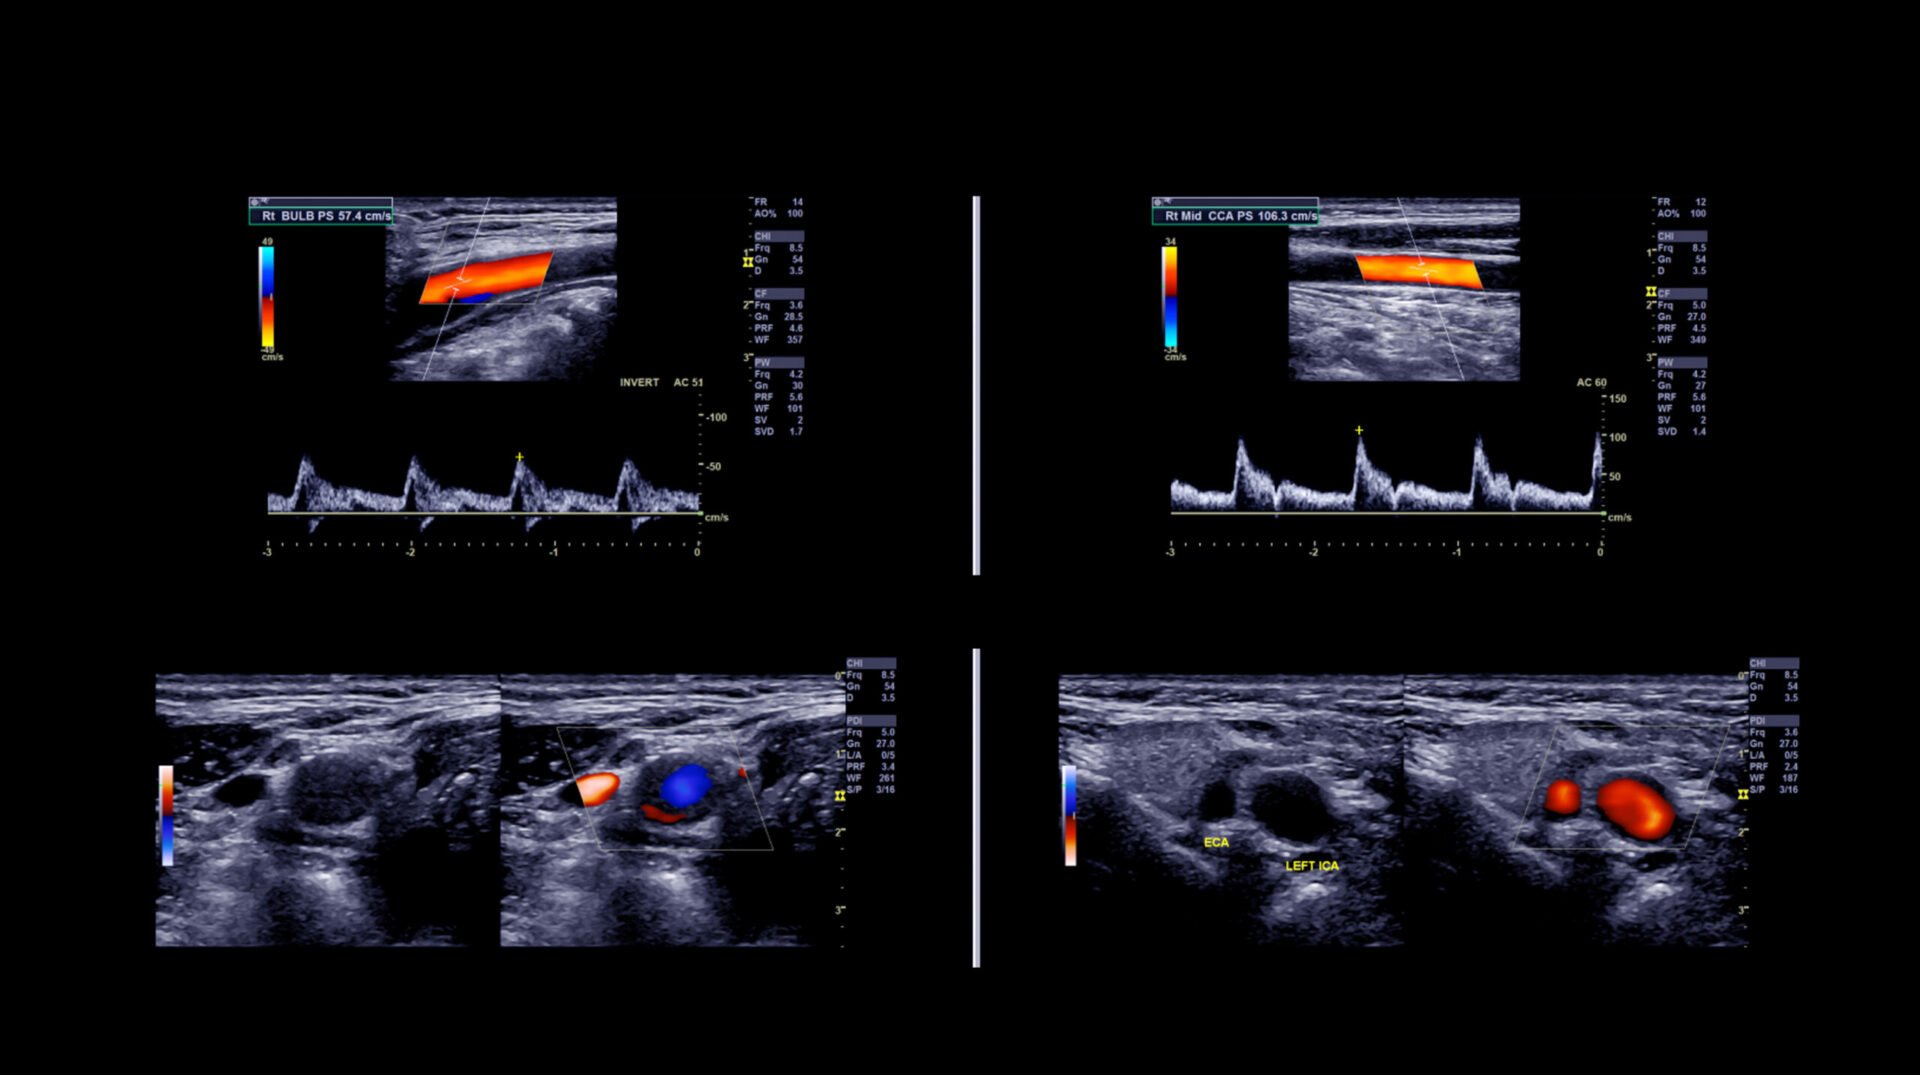

What Does A Vascular Test Consist Of . Vascular studies are tests that check the blood flow in your arteries and veins. In the vascular lab, ultrasound is used to specifically look for circulation (blood flow) problems. Read more about what to expect during a vascular study, such as lying on an exam table, and the doppler transducer pressed against your skin. This means they don’t use any needles. Vascular screenings are essential assessments that evaluate the health and functionality of your blood vessels and arteries, which collectively form the vascular. Vascular tests, also called vascular studies, help us thoroughly assess your condition. Doppler test, vascular lab test, duplex exam, duplex scan, ultrasound, ultrasound exam. Blocked carotid arteries increase your risk of stroke. The results can identify the treatment that will help you. What does a vascular lab exam look for? During a vascular screening, a few different tests are performed to check the health of your blood vessels.

Blocked carotid arteries increase your risk of stroke. Vascular tests, also called vascular studies, help us thoroughly assess your condition. The results can identify the treatment that will help you. Vascular screenings are essential assessments that evaluate the health and functionality of your blood vessels and arteries, which collectively form the vascular. This means they don’t use any needles. Doppler test, vascular lab test, duplex exam, duplex scan, ultrasound, ultrasound exam. What does a vascular lab exam look for? Read more about what to expect during a vascular study, such as lying on an exam table, and the doppler transducer pressed against your skin. During a vascular screening, a few different tests are performed to check the health of your blood vessels. In the vascular lab, ultrasound is used to specifically look for circulation (blood flow) problems.